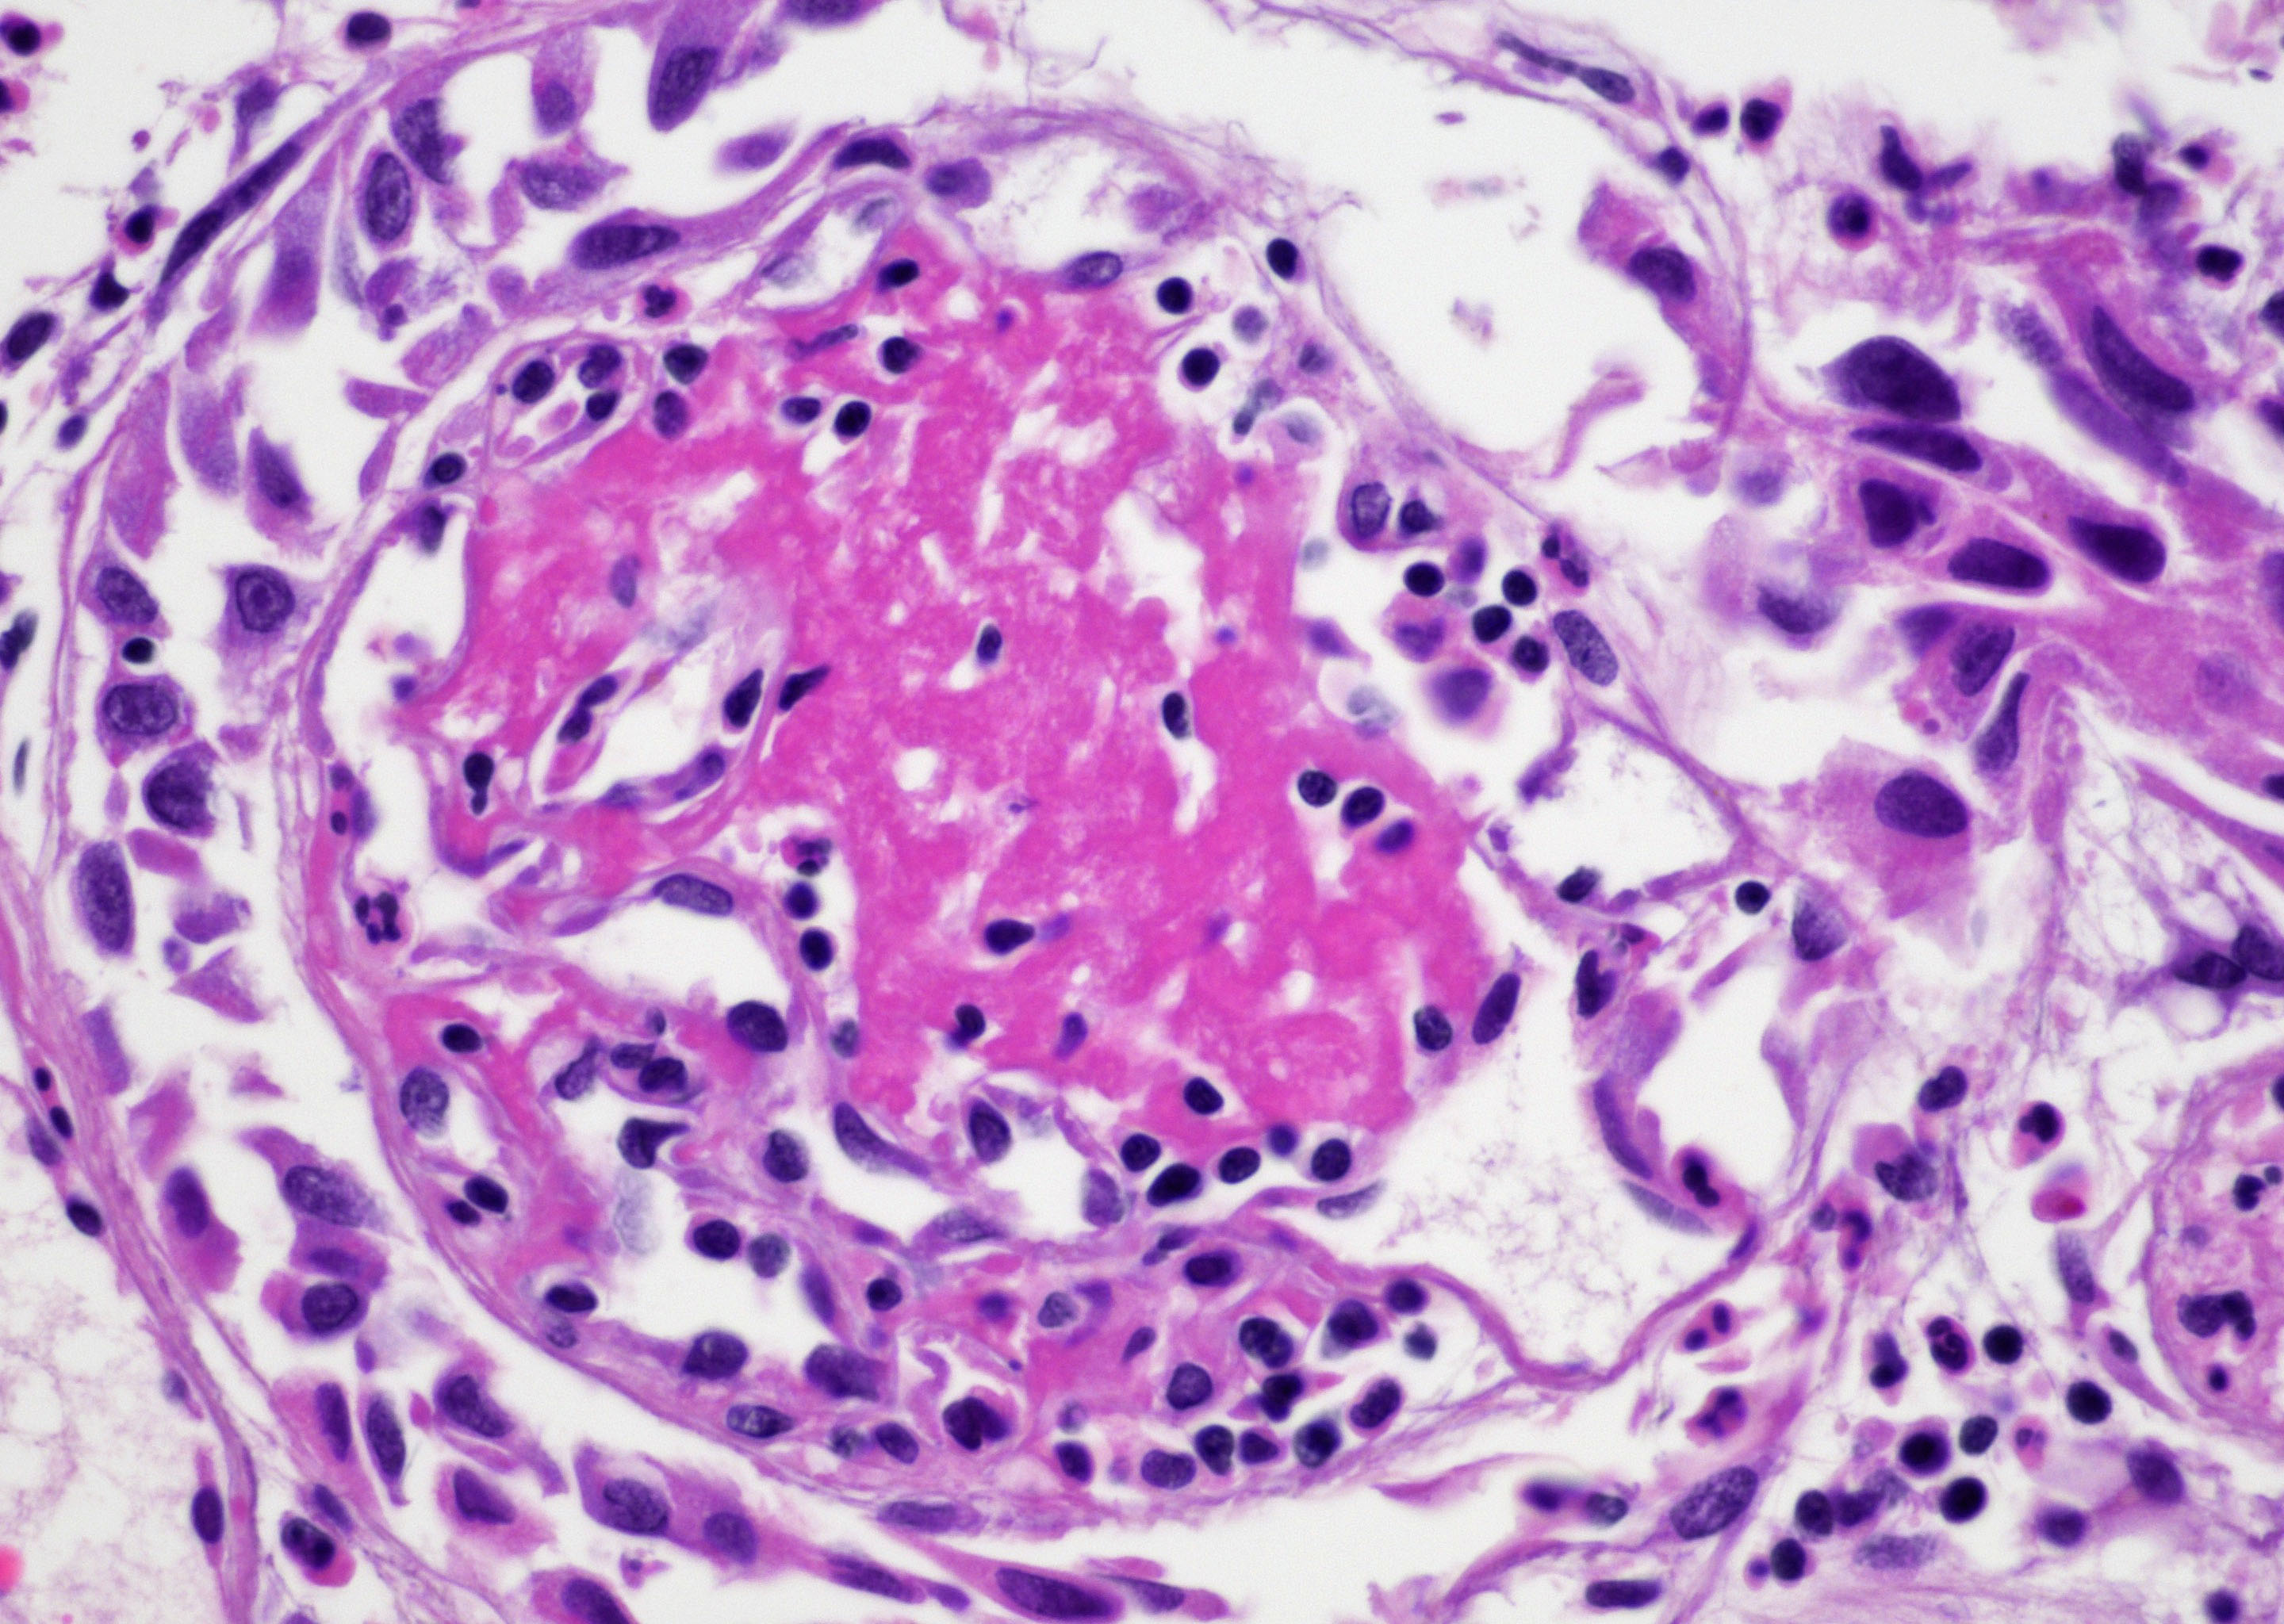

- Vessels with fibrin thrombi, fibrinoid vascular necrosis, vascular congestion, thickened walls, endothelial proliferation and telangiectasia

- Pseudocarcinomatous urothelial hyperplasia: variable sized urothelial cords and nests with rounded or irregular edges present in the lamina propria and enclose dilated blood vessels with fibrin deposition (Am J Surg Pathol 2008;32:92)

- Acute phase: edematous, congested and telangiectatic vessels, acute and chronic inflammatory infiltrate, atypical stromal cells with multinucleated forms

Microscopic (histologic) images

Contributed by Y. Albert Yeh, M.D., Ph.D. and Jennifer Lee, M.D.

Sample pathology report

- Urinary bladder, right wall polypoid lesion, transurethral resection:

- Radiation cystitis with pseudocarcinomatous urothelial hyperplasia (see comment)

- Muscularis propria not identified

- Comment: There is a history of radiation therapy per the medical record. The transurethral resection of the bladder lesion shows fragments of urothelial mucosa with total and partial denudation of urothelium. The urothelial lining cells show reactive changes. There is marked edema, hemorrhage and mixed inflammatory infiltrate composed predominantly of neutrophils and lymphocytes in the lamina propria. Reactive multinucleated stromal fibroblasts are seen. Telangiectatic vessels with fibrinoid necrosis and intravascular fibrin deposition are seen. Anastomosing cords and nests of urothelial cells encircling the vessels with fibrin deposition is evident. Urothelial cells with hyperchromatic nuclei, increased nuclear to cytoplasmic ratio and prominent nucleoli are seen. These features are consistent with radiation cystitis with pseudocarcinomatous urothelial hyperplasia. Muscularis propria is not identified in this specimen.

Board review style question #1

A 68 year old man presented with hematuria and dysuria. He has a medical history of prostate cancer that was treated with radiation therapy. Cystoscopy revealed hemorrhage in the right bladder wall. A transurethral resection of the lesion was performed. A photomicrograph is shown above. What is the diagnosis?

- Cystitis cystica

- Invasive urothelial carcinoma, nested variant

- Radiation cystitis with pseudocarcinomatous hyperplasia

- Urothelial carcinoma in situ

Board review style answer #1

C. Radiation cystitis with pseudocarcinomatous hyperplasia. Answers A, B and D are incorrect because anastomosing cords and nests of urothelial cells encircling ectatic vessels with intravascular and stromal fibrin deposition in a background of mixed inflammation are not present in these entities.